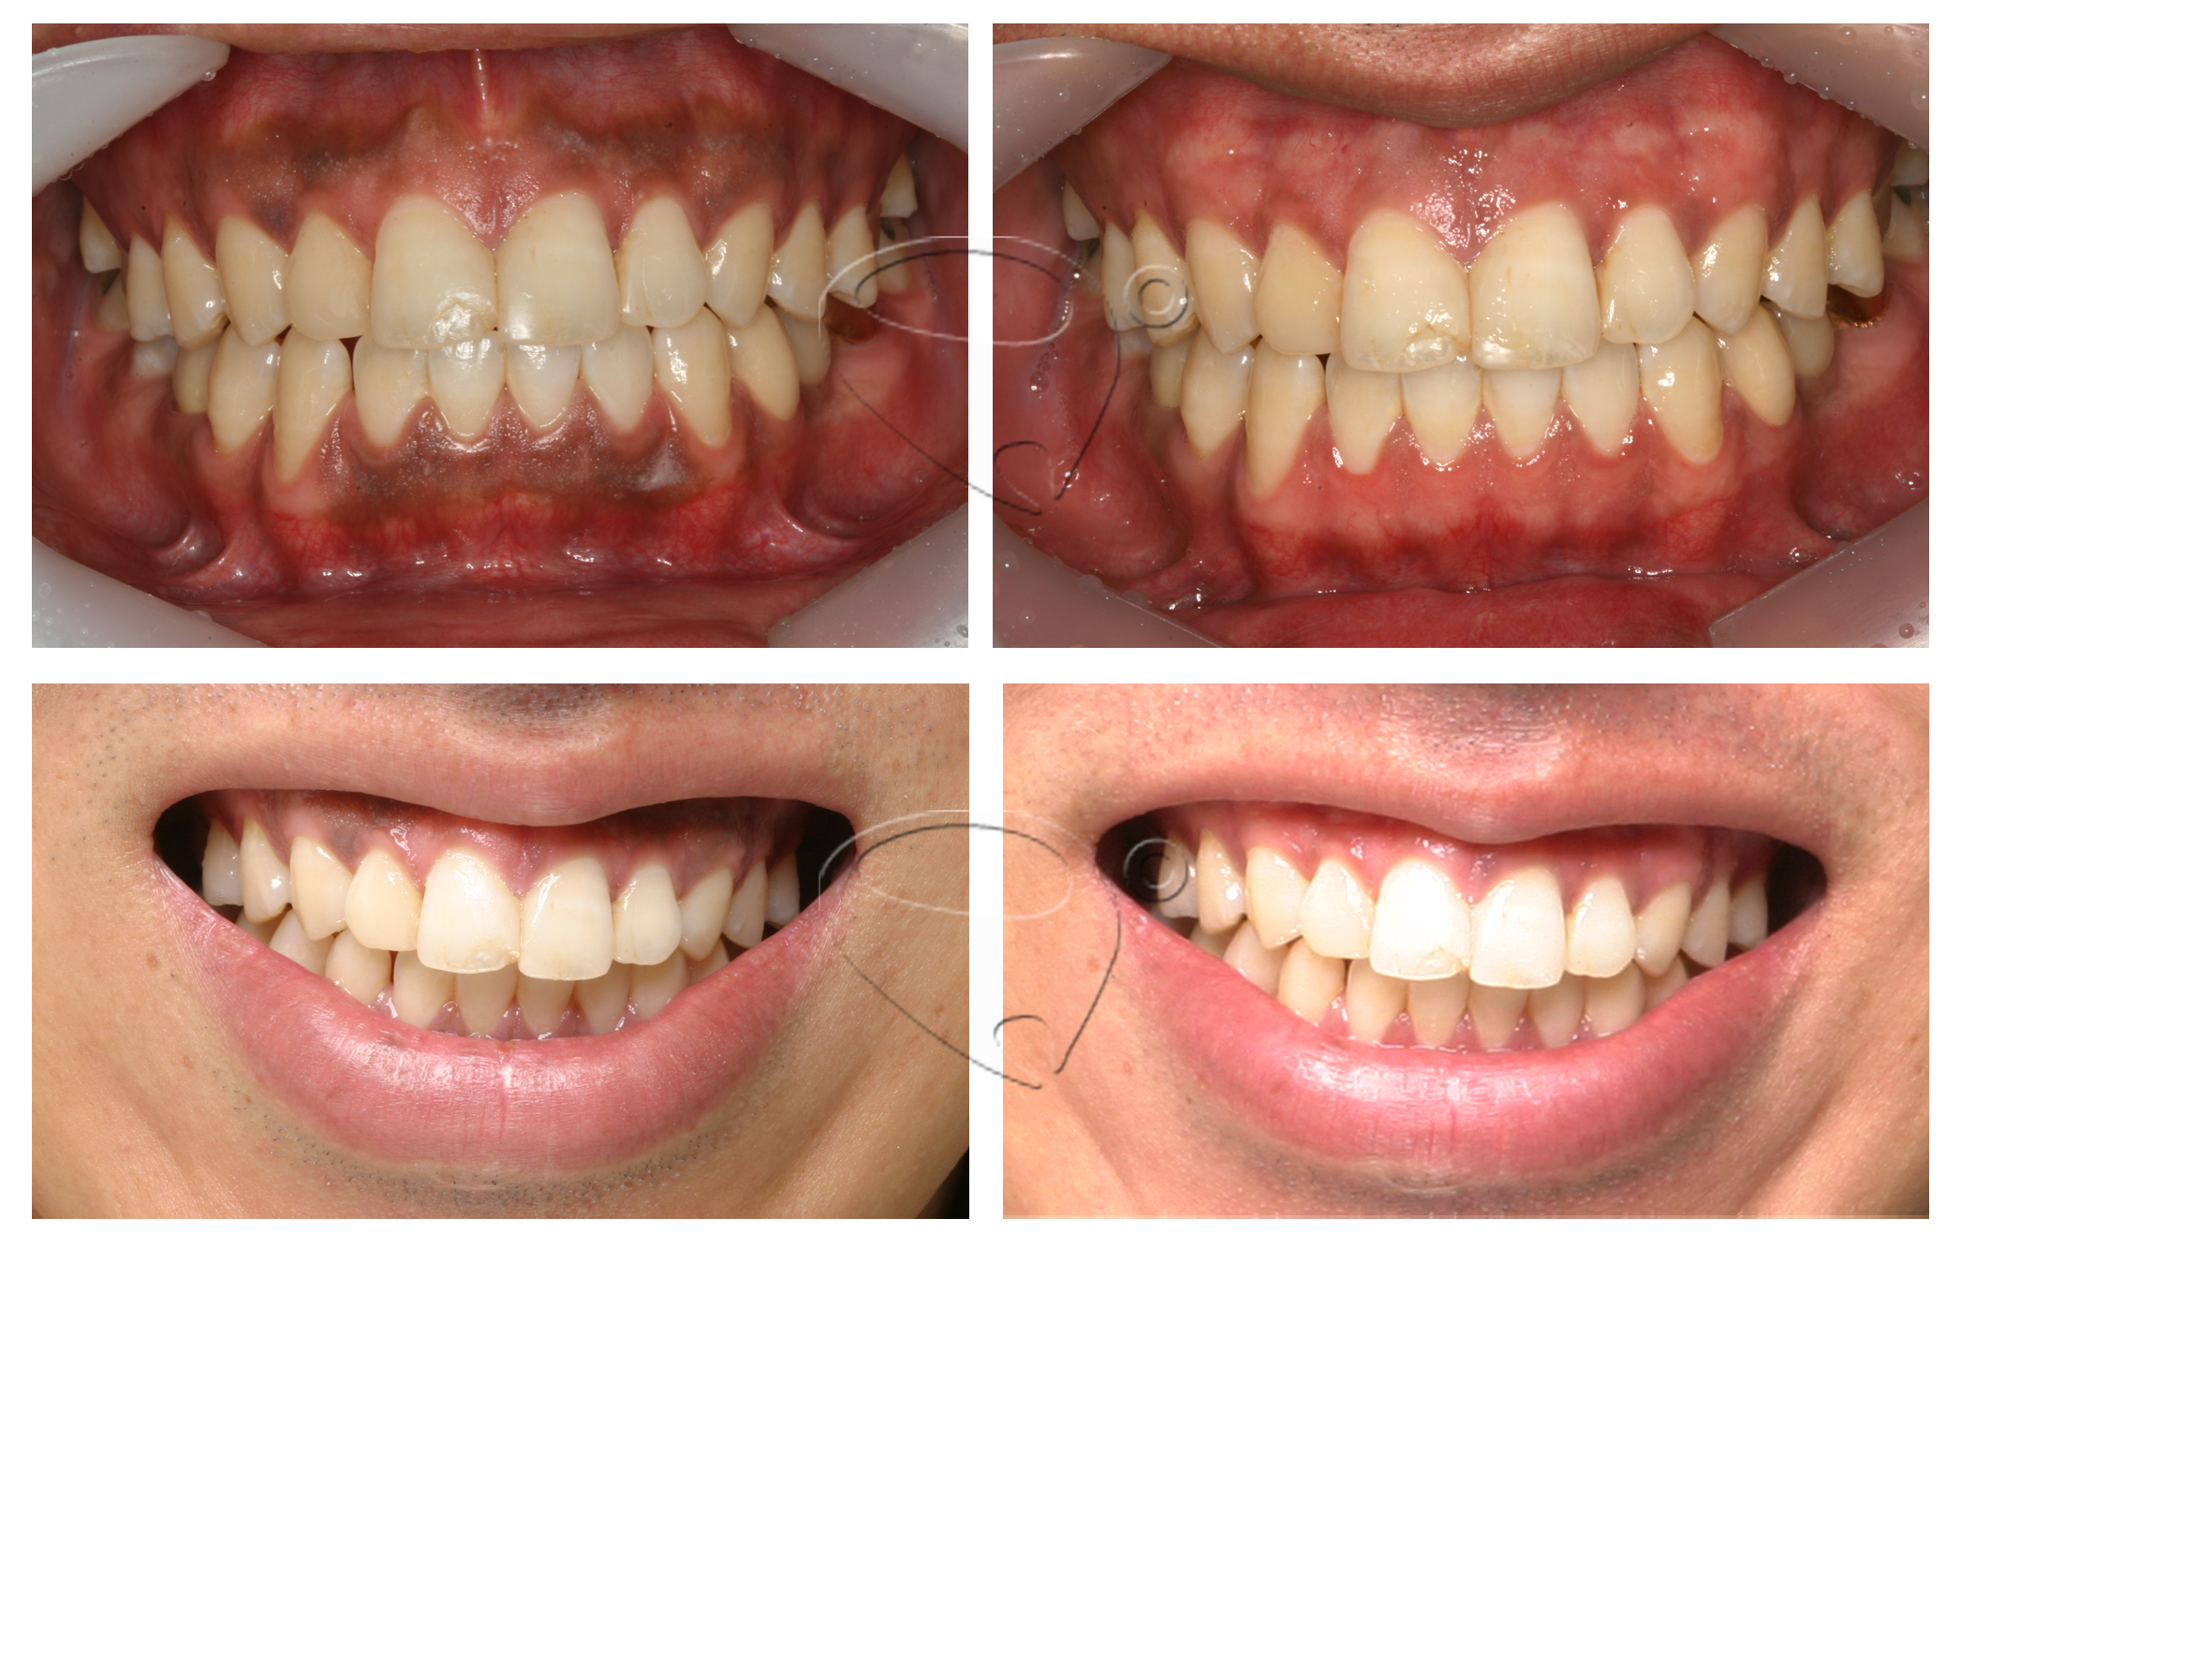

< 레이저 잇몸미백 전. 후 >